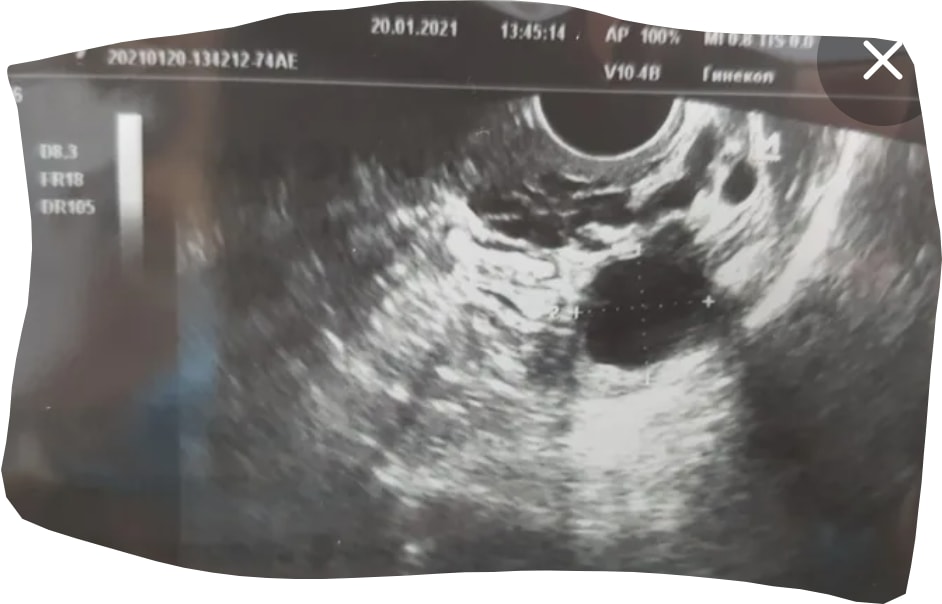

Даша, конечно, доминантный фоликул только слепой может не заметить. Как уже ниже писали, по узи картине он выглядит как чёрная большая дыра

Вот фото для примера, сверху мелкие фоликулы как у вас и один большой доминантный ниже